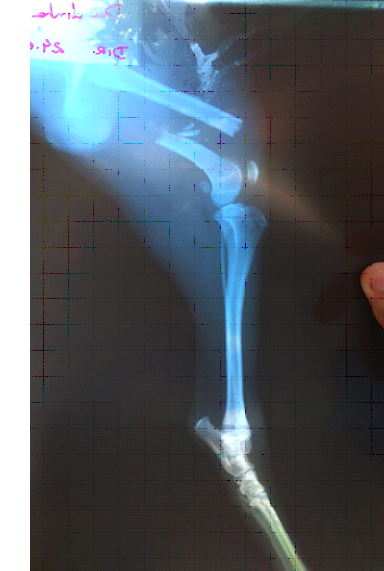

Durante nossa visita ao Hospital (24/07) conhecemos Jessica Prado, 27 anos, que foi acompanhar Dumbinha, cadela de 7 meses que foi atropelada e não recebeu os cuidados necessários. “Sentimos a falta de Dumbinha brincando na rua. Fomos procurar saber dela e descobrimos que tinha sido atropelada. A dona não prestou os primeiros socorros, então eu e meu esposo, que somos vizinhos dela, o fizemos. Viemos para cá para tirar o raio x e eles já identificaram a fratura para poder realizar o procedimento cirúrgico”.

O fato de não ter recebido os primeiros socorros assim que sofreu, agravou o quadro clinico de Dumbinha. "Quando pegamos o resultado do Raio X, vimos a gravidade da fratura.Estamos correndo atrás para ela não ficar assim”, conta. Jessica não poupa elogios ao atendimento: “é nossa primeira vez aqui o atendimento está sendo ótimo. Já coletaram o sangue dela para ajudar a adiantar a cirurgia, só descansaremos quando ela melhorar”, afirma.